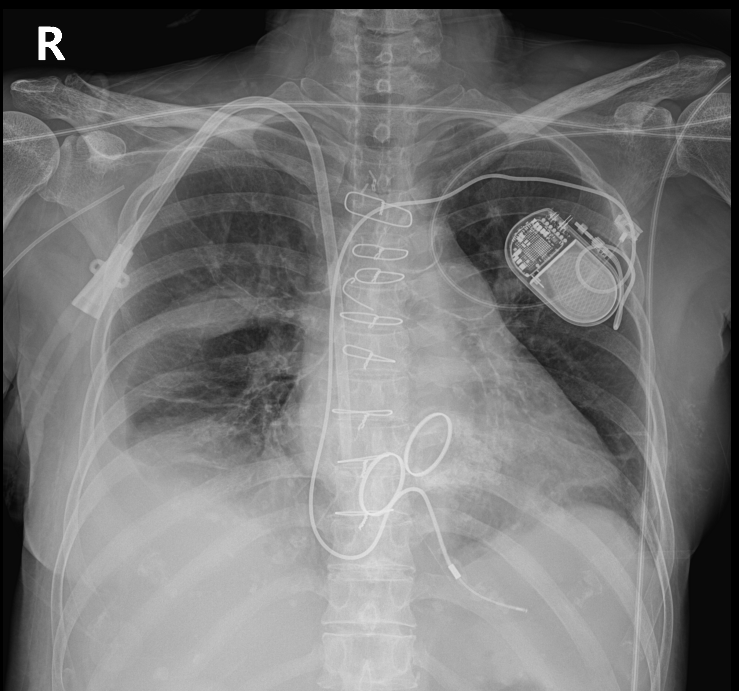

- 심실 빈맥, 심실세동과 같은 치명적인 부정맥, 갑작스러운 심정지에 대한 유일한 치료법은 implantable cardioverter-defibrillator(ICD)를 삽입하는 것이다.